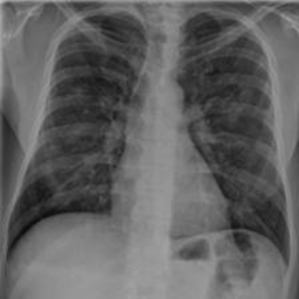

Samples of the dataset are depicted in Figure 3.

Figure 3. An example of an X-ray scan images taken from the dataset (a, b, c) with a label of COVID-19 negative, (d, e, f) COVID-19 positive.